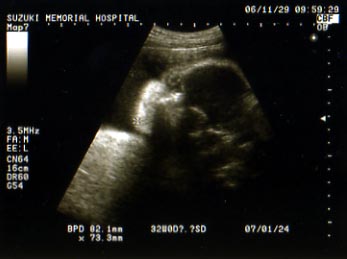

妊婦検診(29w4d)

2006/11/29 (Wed) - 妊娠後期(28w~)

2週間ぶりの検診でございます。

前回は体重増加200gで「よくできました」はんこもらいましたが

今回は前回+1.1㎏でした(がくり)。

まぁ、1ヶ月で見れば1.3㎏だから良しとしよう…。

今日は顔がはっきり見えるエコー写真もらいました。

ちょっと目が不気味なんですけどね。

…ちなみに旦那さんに見せたら「??」だったので

一応解説をいれると

こんな感じです。

どっちに似ているのかは不明(当たり前)。